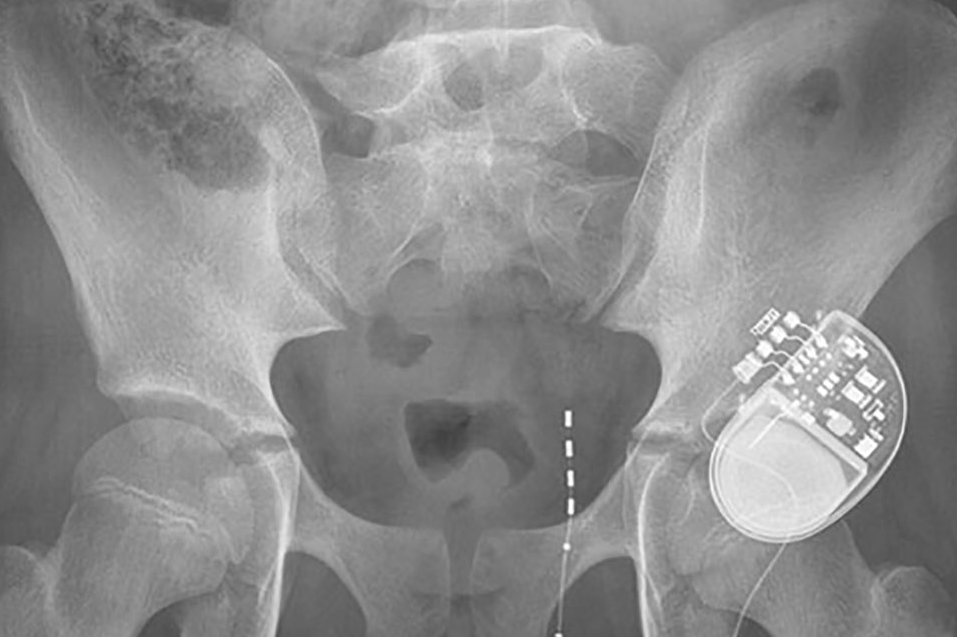

- Sacral Nerve Stimulation

- Sacral Nerve Stimulation Clinic